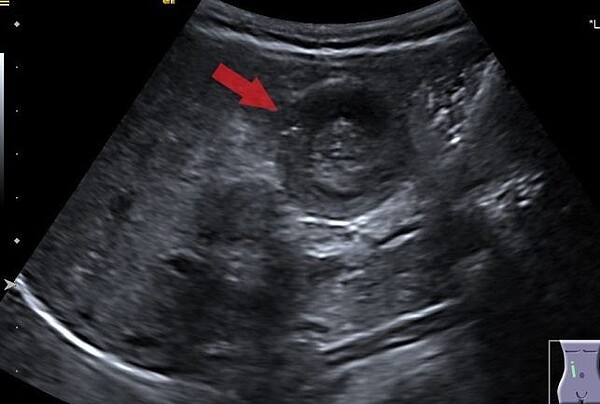

張育瑞還特別提醒家長,對於已經患有胃腸炎的兒童來說,診斷腸套疊也會特別困難,因為急性腸胃炎也有可間歇性腹痛或者嘔吐。當無法區分急性腸胃炎跟腸套疊時,進一步的影像檢查就相當必要,而超音波檢查是檢測腸套疊的首選方法。在超音波中看到“同心圓”或“甜甜圈”的影像,代表腸內的腸層已經套住並黏膜重疊,才會產生如此影像。